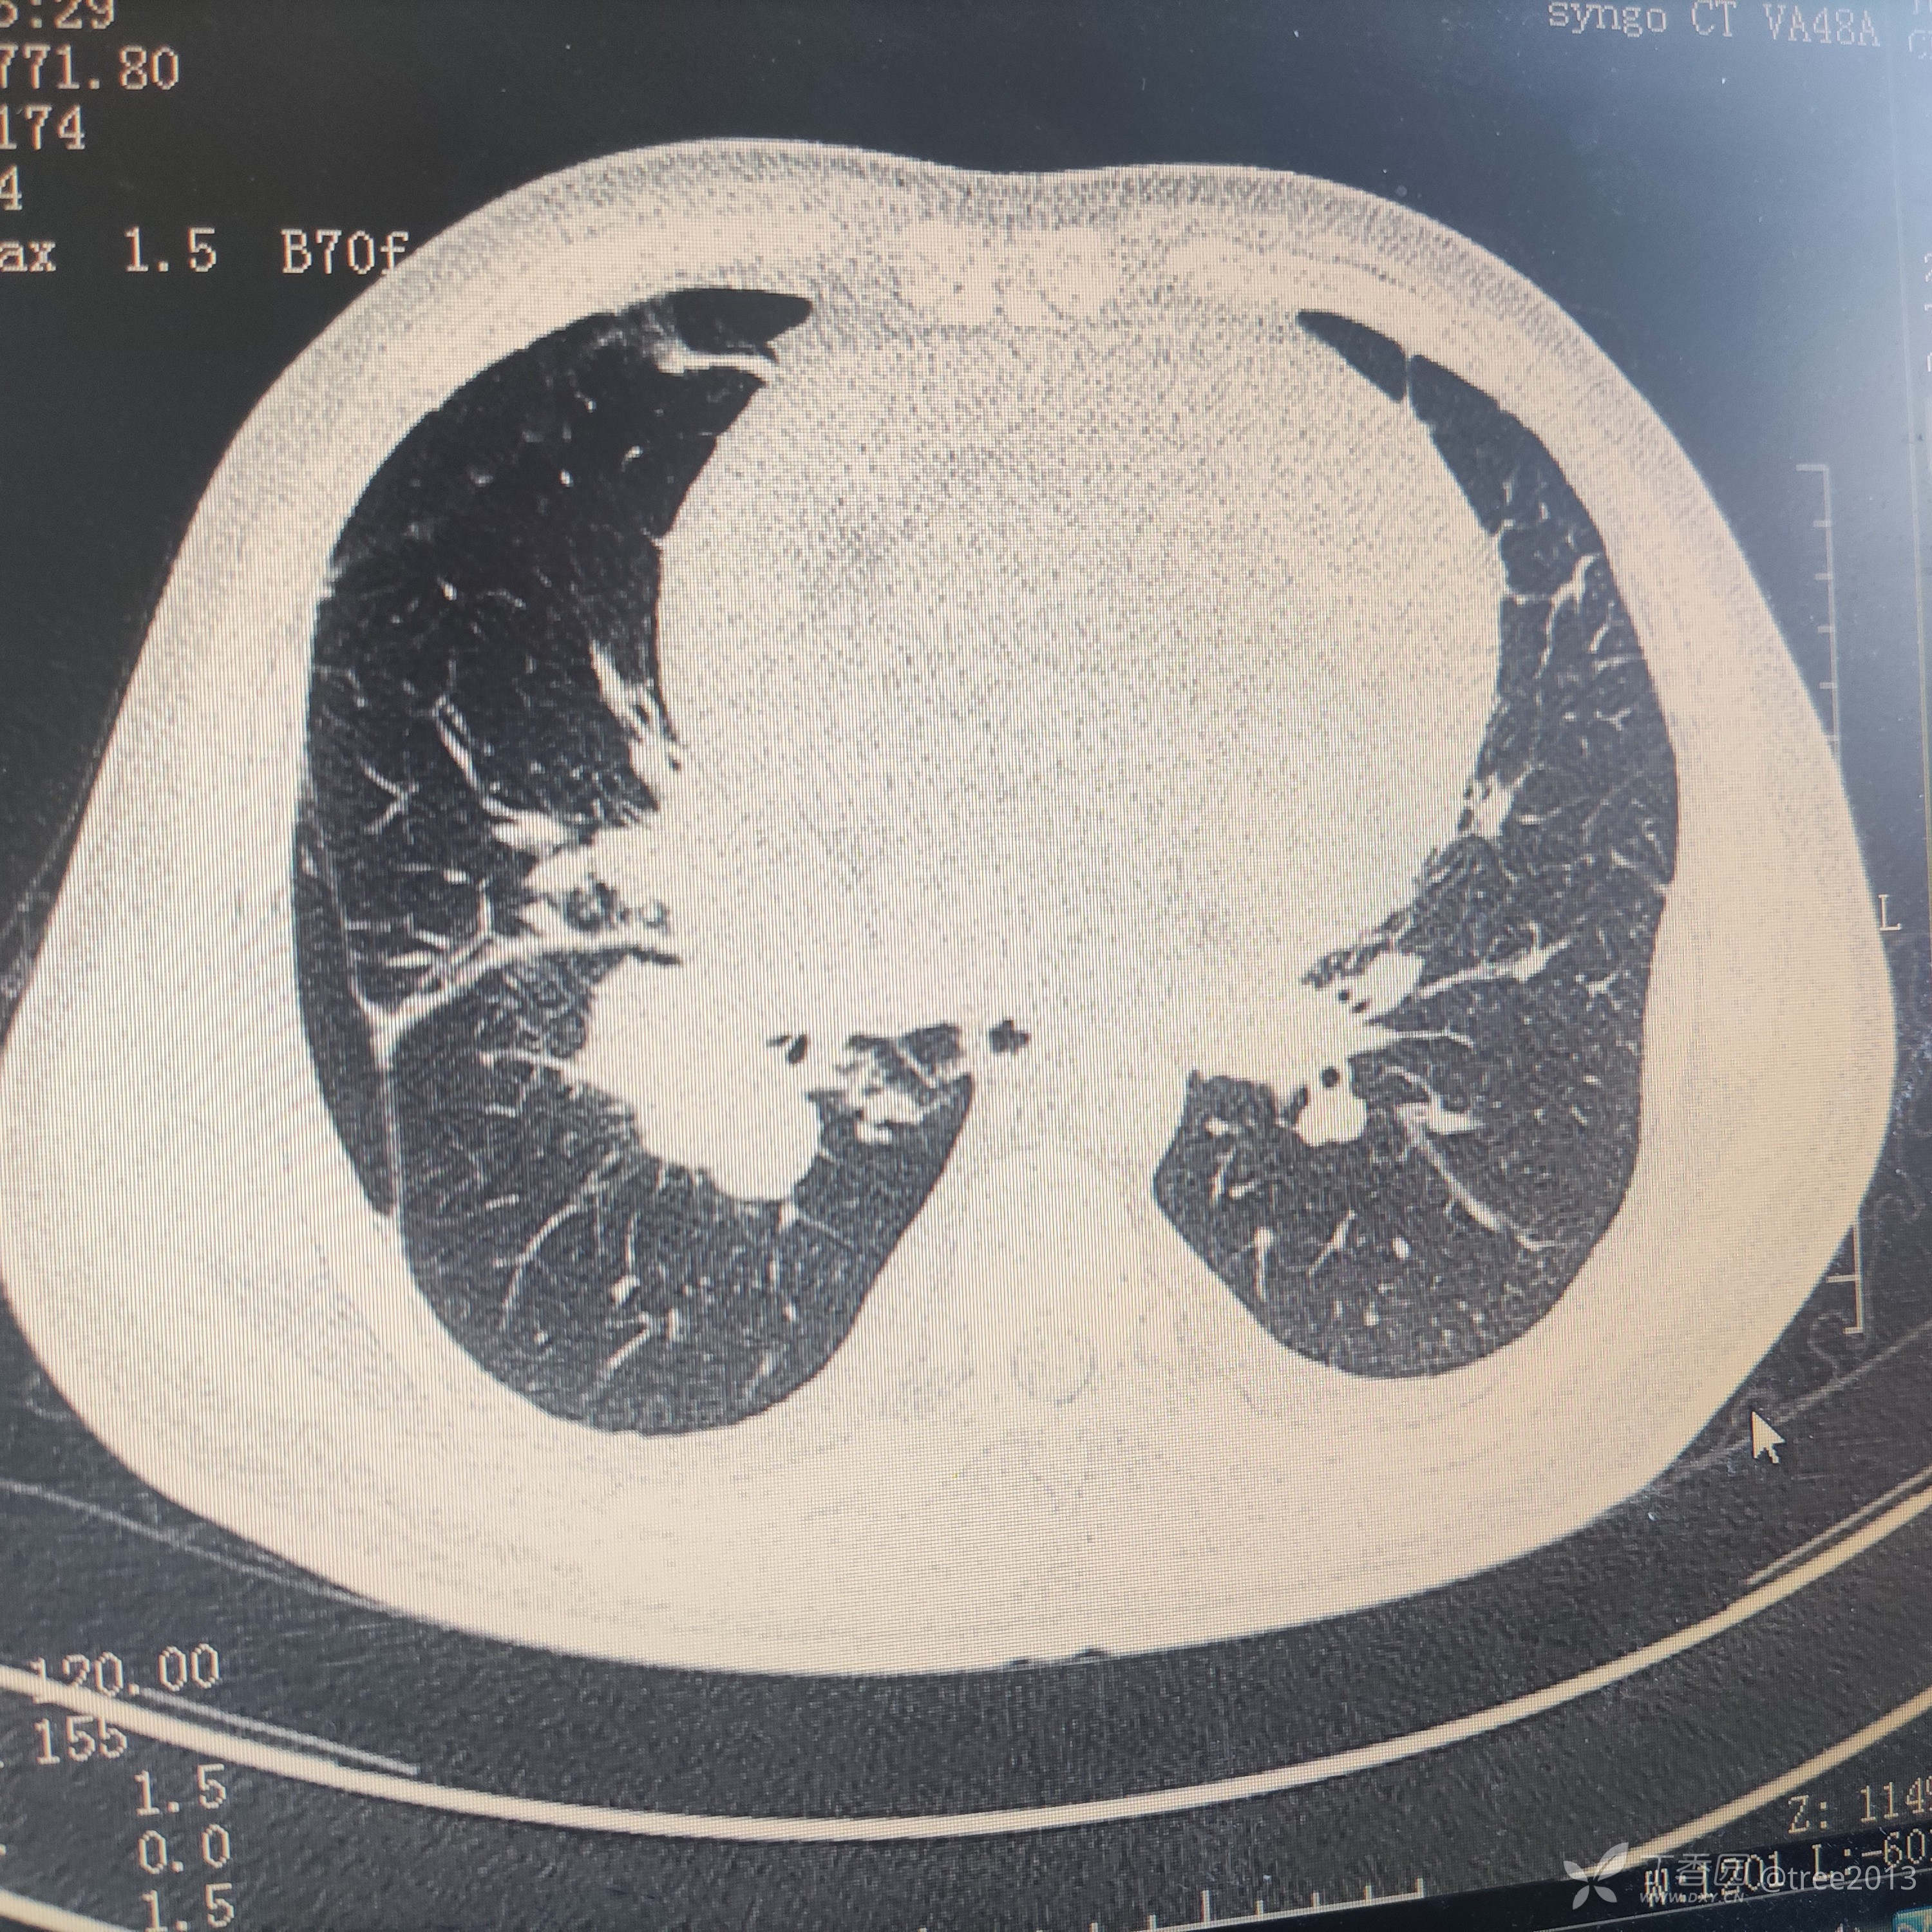

胸部CT:

诊断:肺部恶性肿瘤伴多大转移 心包积液 胸腔积液